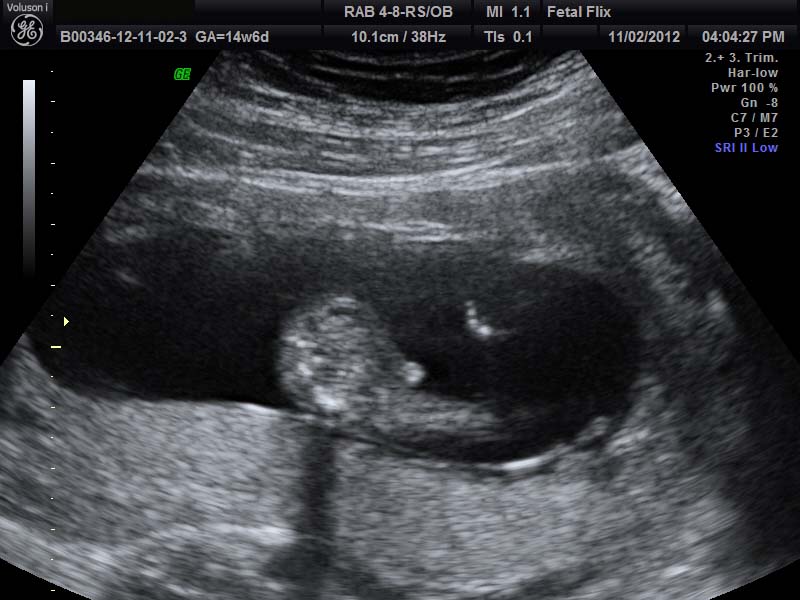

I would told boy, but baby only measured 14w2d. Any thoughts???

boy its early but nub and potty shots 100% boy

Yeah, looks like something is sticking out in the first pic and second picture looks like a boy nub. :)

Not sure to be honest, the potty shot reminds me of girl bits protruding which the would at this age, and the nub shot, I don't see one

This is my 14 w 6 day boy shot....mine looks a lot different than yours!